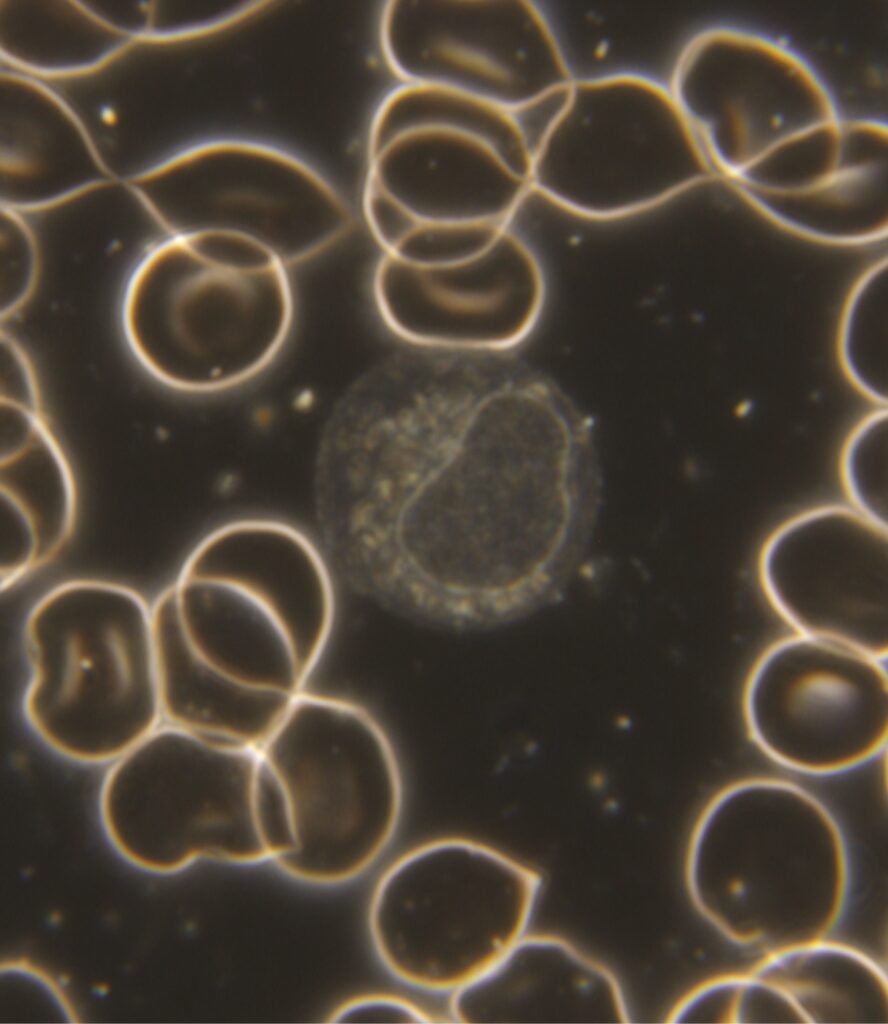

LGL Lymphozyt

Bei viralen Belastungen (Infektionen) wird ein bestimmter Typ von Blutzellen vermehrt gebildet. Diese Zellart gehört zu den Lymphozyten, die im Blut immer vorhanden sind. Im Falle einer viralen Infektion wird ein Teil der Lymphozyten größer als normal gebildet. Dieser spezielle Lymphozyt wird LGL-Zelle (Large Granular Lymphocyte) oder auch passenderweise Virozyt genannt. Wenn diese Zellart vermehrt im Blut auftaucht, dann liegt sehr häufig eine virale Belastung vor. Je mehr von den Virozyten auftreten, um so höher ist die virale Last. Es kann zwar nicht unter den Viren differenziert werden, aber die Information, dass ein virales Geschehen im Organismus stattfindet, hat seit über einem Jahr eine besondere Bedeutung bekommen. Dieser Zelltypus sieht einer anderen Zellart, den Monozyten sehr ähnlich und sollte nicht mit diesem verwechselt werden. Im rechten Bild ist diese Zellart abgebildet. In unseren Ausbildungsseminaren kann man diese Differenzierung und die weitere Erkennung von Auffälligkeiten erlernen.